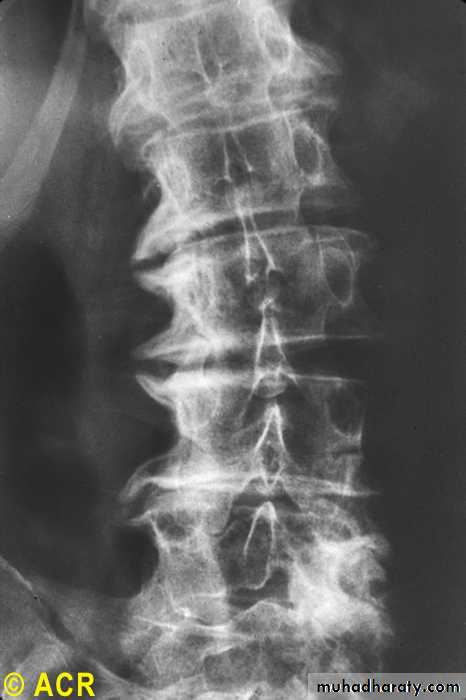

Osteoarthritis:lumbarvertebrae,advancedstages